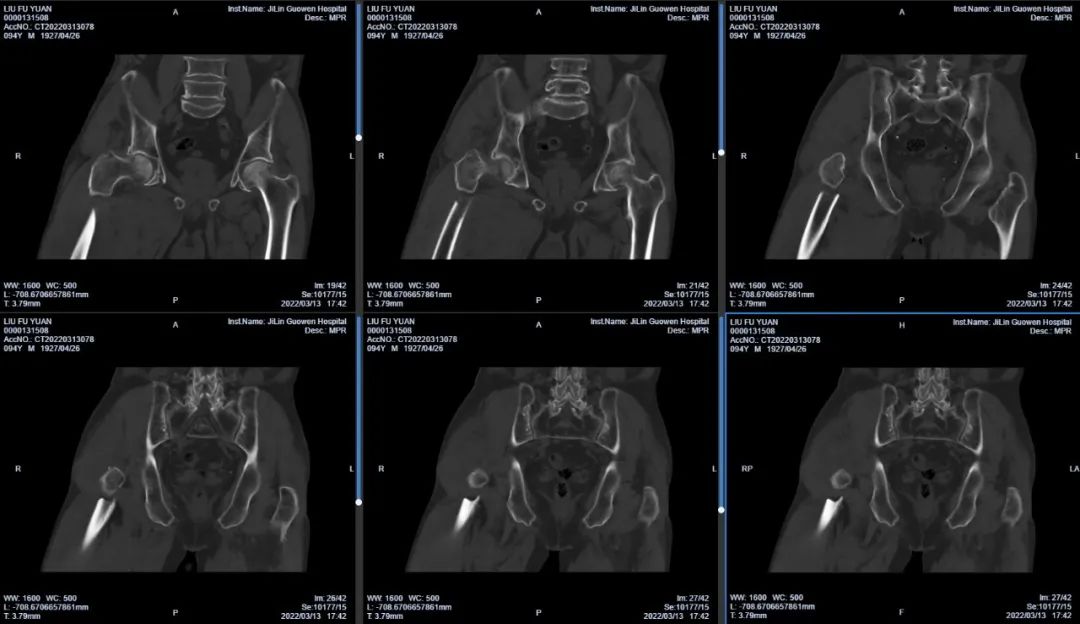

3月13日伴著急促的腳步聲、轆轆的車輪聲,夾雜著患者痛苦的呻吟聲,一位94歲的高齡老人被急診科醫(yī)護(hù)人員緊急送至骨科療區(qū)。這是怎么回事?呂國褔主任帶著值班醫(yī)生在做好防護(hù)措施后,第一時間來到患者病床前,經(jīng)急診科醫(yī)生診斷告知為 “股骨近端粉碎性骨折”,患者右大腿近端嚴(yán)重畸形,骨折端已經(jīng)刺穿前方肌肉直達(dá)皮下,局部皮膚高高隆起,局部皮膚有挫傷灶,呈青紫色,皮膚變薄,皮膚外可明顯觸及骨折斷端,右股骨X線片示:右股骨近端粉碎性骨折,斷端移位明顯,斷端銳利,近斷端位于前方皮膚下,局部皮膚隆起。患者疼痛劇烈,痛苦難耐,測生命體征:血壓:220/110mmHg。